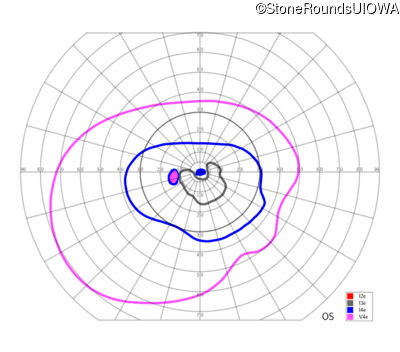

Congenital Stationary Synaptic Dysfunction (IA2g)

Congenital Stationary Synaptic Dysfunction (IA2g)

| Congenital Stationary Synaptic Dysfunction | CABP4 | Arg49Stop CGA>TGA | IVS1+1 G>T | AR |